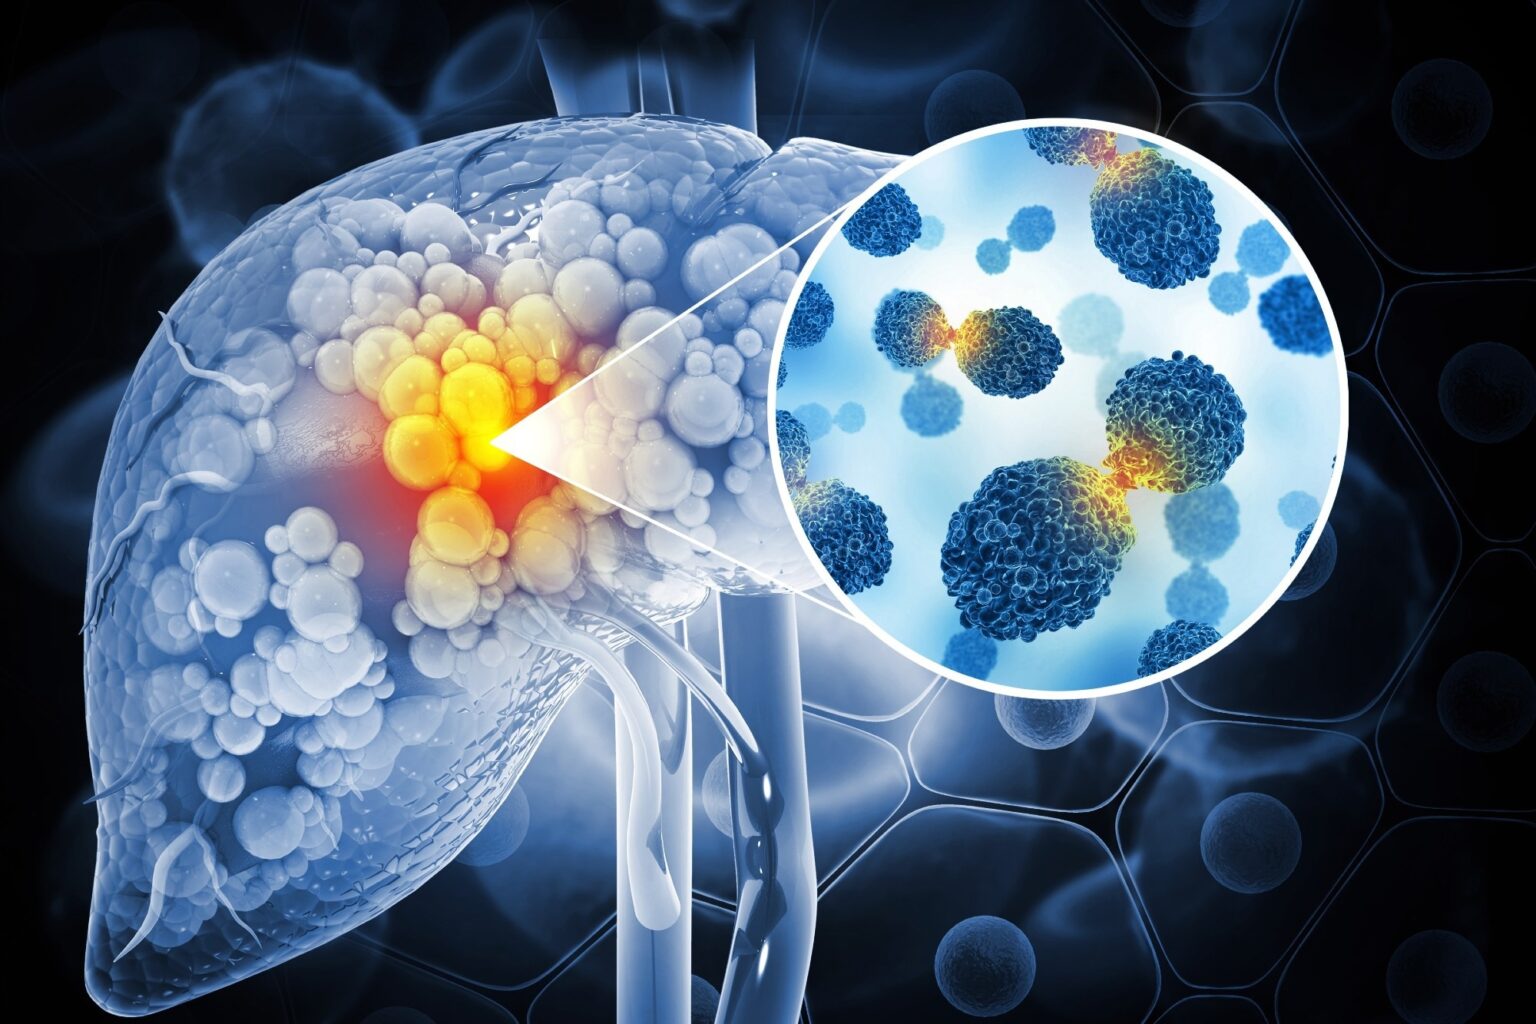

A new ultrasound-guided nanotherapy wipes out liver tumors while training the immune system to keep them from coming back.

Image Credit: crystal light/Shutterstock.com

The study, published in Nano Today, introduces a biodegradable nanoparticle system that combines sonodynamic therapy and cell death induction (ferroptosis) to treat hepatocellular carcinoma, the most common type of liver cancer.

Hepatocellular carcinoma is one of the most challenging types of liver cancer to treat due to poor immune responsiveness and high recurrence.